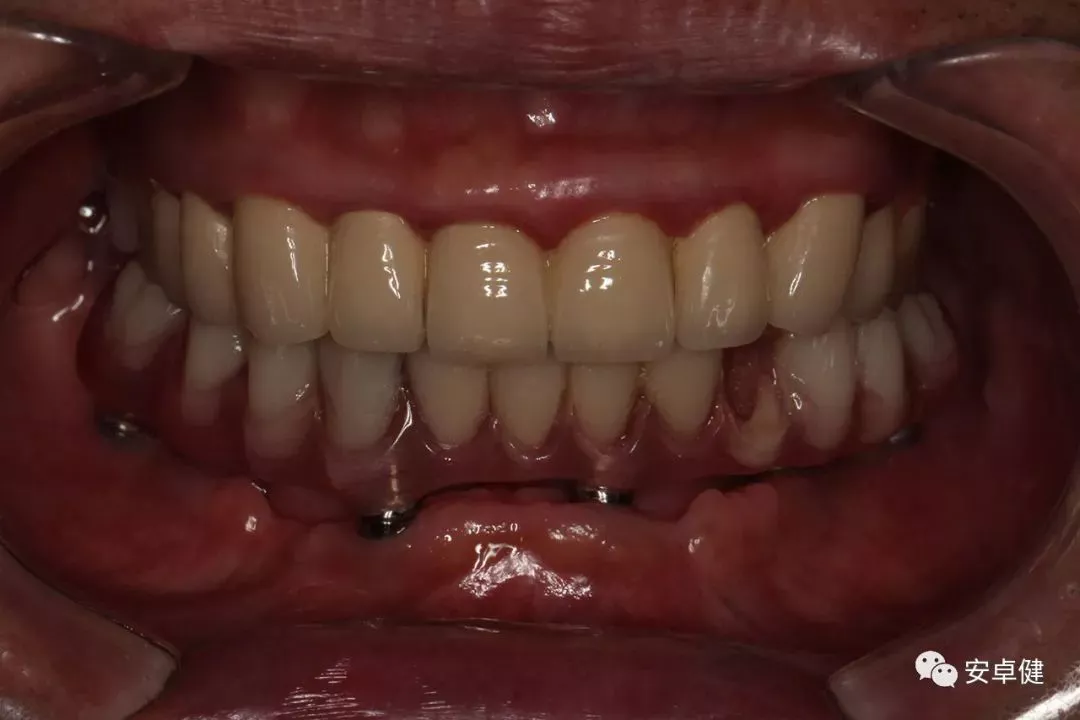

戴最终修复体正面咬合照

戴牙后4个月复诊正面咬合照

• 随访可见患者口腔卫生状况可,牙龈无红肿;

• 下颌修复体状态良好,无修复体机械并发症;

• 种植体基台稳定性良好,无松动;

• 种植体无松动,周围无红肿、溢脓及疼痛表现;

• 正中、前伸及侧方咬合检查可见咬合印记分布均匀,咬合关系良好;

• 患者反映日常使用良好,舒适性佳,满意度高。